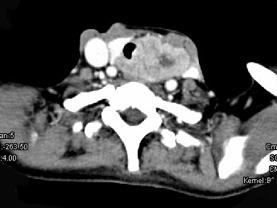

问题 女,50岁,左下颈部扪及一质硬、表面高低不平的包块,约半年,肿块逐渐增大,现感吞咽困难。如图所示CT诊断为()

选项 A.甲状腺癌 B.食管癌 C.喉癌 D.甲状腺原发淋巴瘤 E.颈部神经鞘瘤

答案 A